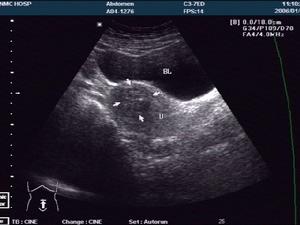

一、超声检查

目前国内B超检查较为普遍。鉴别肌瘤,准确率可达93.1%,它可显示子宫增大,形状不规则;肌瘤数目、部位、大小及肌瘤内是否均匀或液化囊变等;以及周围有否压迫其他脏器等表现。由于肌瘤结节中肿瘤细胞单位体积内细胞密集,结缔组织支架结构的含量及肿瘤、细胞排列不同,而使肌瘤结节于扫描时表现为弱回声,等回声和强回声3种基本改变。弱回声型是细胞密度大,弹力纤维含量多,细胞巢状排列为主,血管相对丰富。强回声型,胶原纤维含量较多,肿瘤细胞以束状排列为主。等回声型介于两者之间。后壁肌瘤,有时显示不清。肌瘤愈硬衰减表现愈重,良性衰减比恶性明显。肌瘤变性时,声学穿透性增强。恶变时坏死区增大,其内回声紊乱。故B超检查既有助于诊断肌瘤,区别肌瘤是否变性或有否恶性变提供参考,又有助于卵巢肿瘤或其他盆腔肿块的鉴别。